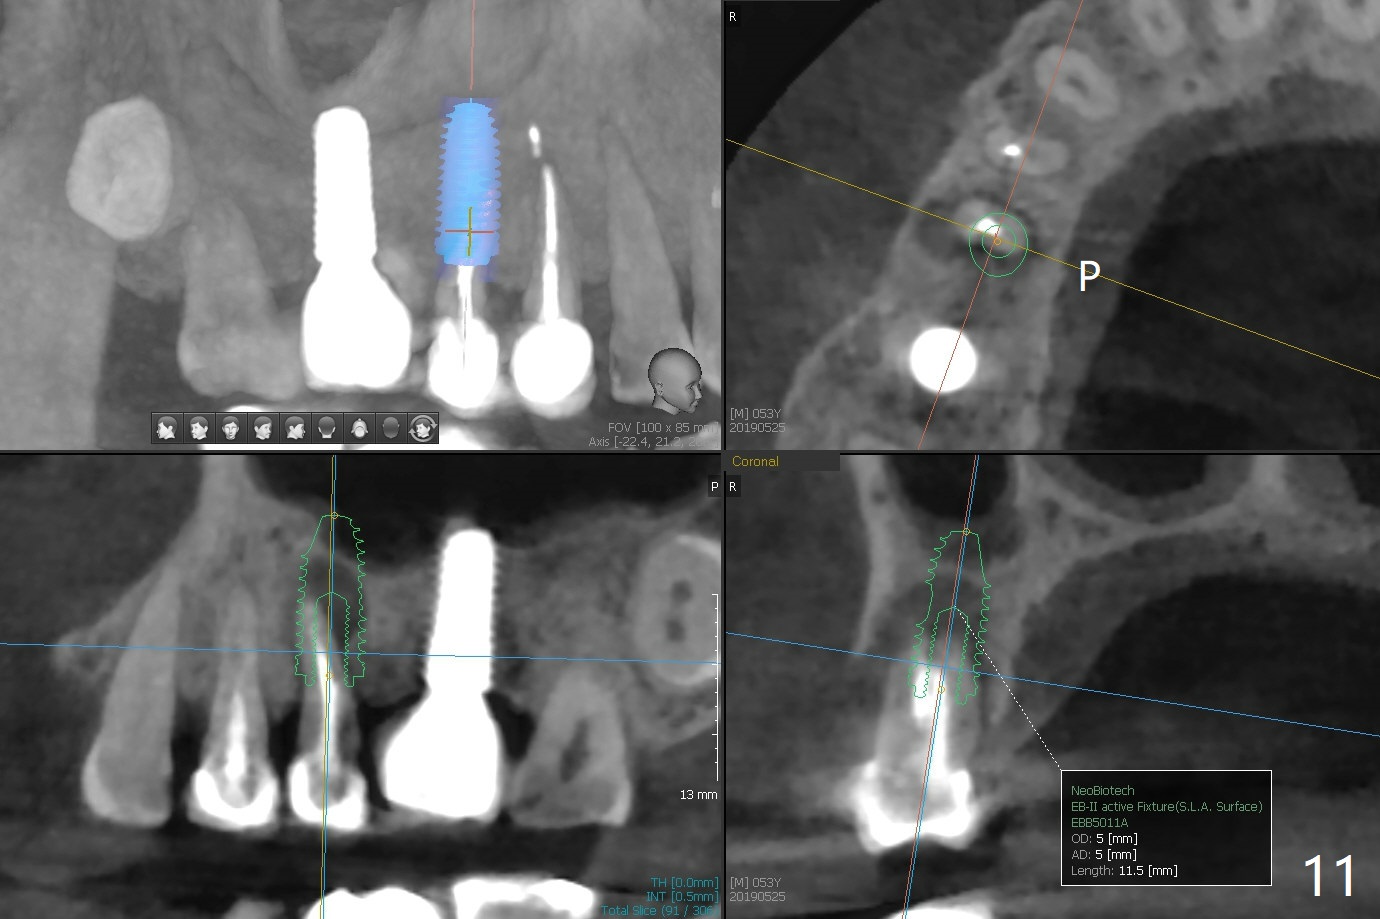

Crown/Implant Ratio

A 53-year-old man has signs of bruxism (Fig.1 diastema *) and root fracture or RCT failure at #4 (Fig.4 (large PARL *)). The RCT failure is related to overload of the affected tooth, which is in turn partially due to infraocclusion of the neighboring implant crown (Fig.1 arrows (implant positioning not ideal)) and partially to due to partial edentulism (Fig.2 missing teeth #14 and 18). For long term, limited ortho will be performed to upright and distalize the tooth #15 (Fig.3 arrow), followed by implants at #14 and 18. For now, the tooth #4 will be extracted (Fig.5), followed by osteotomy in the distal slope of the socket with guide (Fig.6 to get good trajectory). To place a bone-level implant (Fig.7 green), an abutment (blue) with long cuff (pink) is to be used. With poor implant/crown (white) ratio, stress occurs at the junction of the implant/abutment (red arrow), resulting in easy abutment screw loosening. In contrast, stress may be applied to directly to a tissue-level implant (Fig.8 arrow) with less likelihood of abutment screw loosening. The implant/crown ratio improves by approximately 5.5 mm. The roots of the teeth #15 and 16 are so close to each other that interference may occur when the tooth #15 is being uprighted (Fig.9). The empty socket of the tooth #4 is wide buccopalatal (Fig.10); the buccal plate is resorbed coronally (Fig.10 <) so that a 4.5 or 5 mm diameter implant should be placed palatal (Fig.11). Use sticky bone to repair the buccal plate defect and PRF membrane or plug for sinus lift. Following #15 uprighting and distalization, a 5x10 mm implant will be placed at #14; the ridge is triangular (Fig.12 <) so that bone trimmer is needed. A 10 mm long implant will be placed at #18 (Fig.14) to avoid perforating to the submandibular fossa (Fig.13 *).